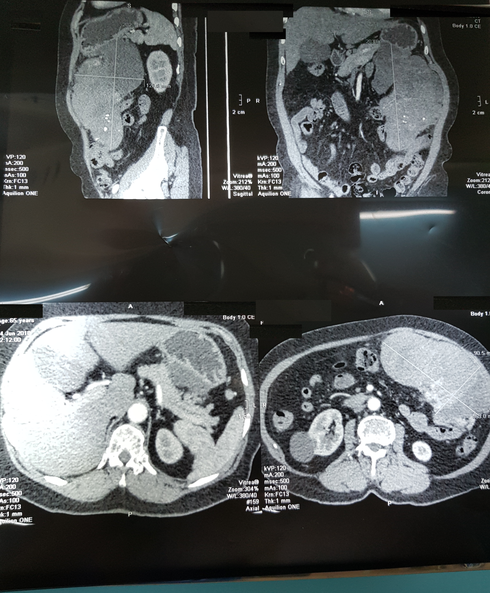

Hình ảnh khối bướu qua chụp CT scan |

Bên cạnh đó, kết quả CT scan khảo sát vùng bụng phát hiện khối u mô đệm thành dạ dày, choán chỗ toàn bộ vùng hạ sườn trái, có đường kính lớn nhất lên tới 20cm. Để khẳng định chẩn đoán, bà L. được chuyển đến Bệnh viện Bình Dân để nội soi dạ dày-tá tràng, kết quả cho thấy một khối u dưới niêm mạc dạ dày dạng u mô đệm đường tiêu hóa (GIST-Gastrointestinal Stromal Tumor).